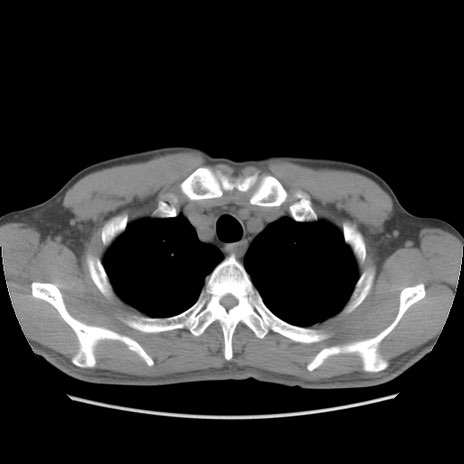

症例56 CT(横断像)

脂肪ウインドウ